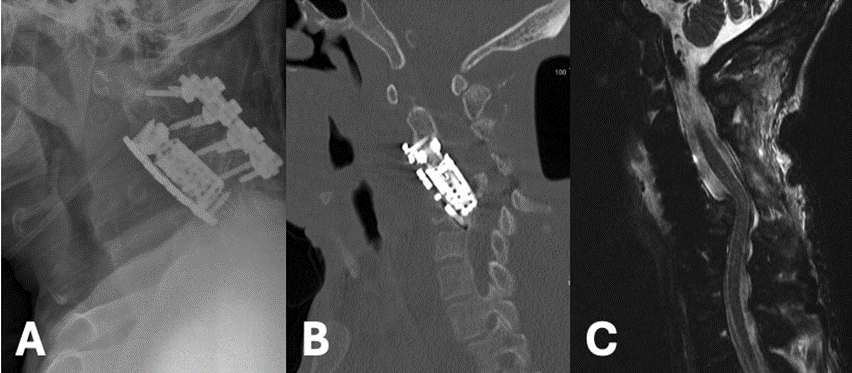

52-year-old male with past medical history significant for diabetes mellitus (DM), end-stage renal disease (ESRD), heart failure with preserved ejection fraction (HFpEF), deep venous thrombus (DVT) with inferior vena cava (IVC) filter presented to the hospital with a chief complaint of bilateral upper extremity (BUE) deltoid weakness with associated paresthesias and bowel incontinence for six days. Past surgical history significant for revision C3-C5 ACCF and C2-C5 posterior cervical fixation one month prior for methicillin-resistant staphylococcus aureus (MRSA) osteomyelitis. Cervical x-ray (XR) and computed tomography (CT) Cervical Spine discovered subsidence of the corpectomy hardware and cervical kyphosis resulting in retropulsion of the bone and hardware (Figure 1A and B). MRI Cervical Spine confirmed severe canal stenosis and draping of the spinal cord over the retropulsed fragment (Figure 1C). The patient was placed in cervical traction using Gardner-Wells tongs, which improved the cervical kyphosis and the patient’s neurologic exam. On hospital day (HD) one, the patient was taken to the operating room for revision corpectomy to include C3-C6 and extension of the posterior cervical construct. Post-operatively, the patient regained full strength and sensation. CT scan completed on post-operative day (POD) three demonstrated early subsidence and thus the patient was placed in a halo brace (Figure 2). Unfortunately, patient’s hospital course was complicated by worsening gastrointestinal bleeding and ultimately septic shock. He passed away one month following surgery.

Figure 1: Lateral XR (A) and Sagittal CT Cervical Spine without Contrast (B) Demonstrating severe subsidence of the cervical cage with retropulsion, C5 fracture, and the resulting severe kyphotic deformity. Sagittal T2 MRI Cervical Spine without Contrast shows severe cervical canal stenosis and draping of the cervical cord over the retropulsed fragment (C).